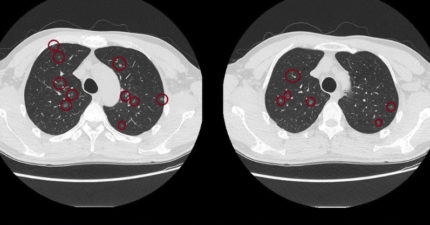

才50歲!男無症狀做健檢 斷層震驚醫:肺結節上百顆

知識

,

台灣

January 7, 2026